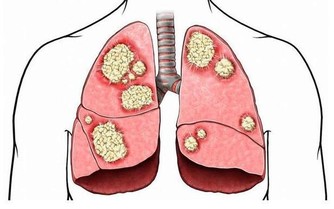

現代人飲食過度油膩,加上缺乏運動、不良生活習慣等,導致體內脂質缺乏良好的代謝途徑。高血脂是指血中膽固醇、三酸甘油脂等指標出現異常,原因可能是先天遺傳因素,或是後天飲食、疾病、服用藥物、不良生活習慣所致。但是到底什麼造成了高血脂,不外乎以下的三點。

【血脂過高,我們的身體會出現什麼樣的狀況,若有下面的幾種信號,就是血脂過高造成的】